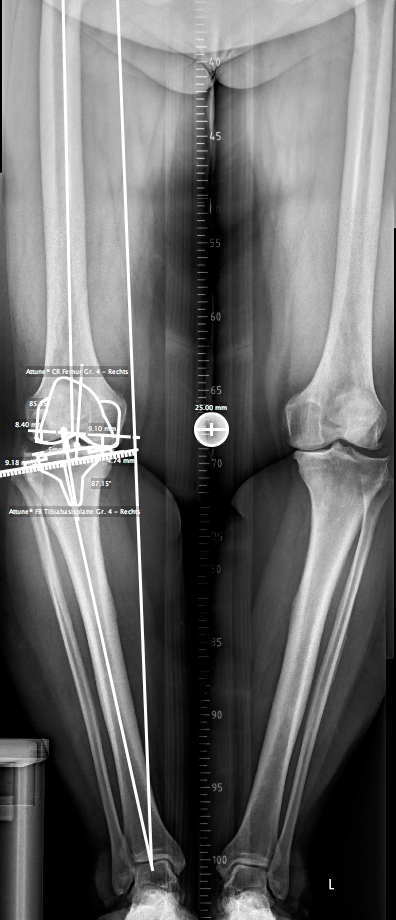

Orthopädisches Gutachten: Bezieht sich auf die Diagnose, Behandlung und Prognose von Erkrankungen des Bewegungsapparates, insbesondere der Gelenke, Wirbelsäule und Muskeln. Ein orthopädisches Gutachten wird häufig erstellt, wenn es um chronische Erkrankungen wie Arthrose oder Probleme nach Operationen geht.